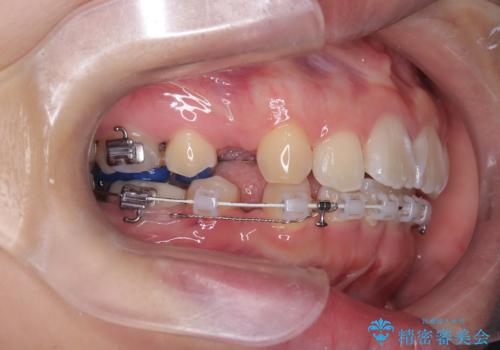

- 口元が出ている(突出している)ことを気にされて来院されました。精密な検査の結果、前歯を大きく後退させるスペースが必要と診断。患者様の**「前歯を下げたい」という強いご要望に応えるため、上下左右の第一小臼歯を抜歯し、そのスペースを利用して前歯を奥へ移動させる治療計画を立案しました。また、人目を気にせず治療できるよう、上顎に裏側矯正、下顎に表側矯正を組み合わせたハーフリンガル矯正**を提案しました。

今回の矯正治療では、前歯を大きく後退させるスペースを確保するため、計画通り上下左右の第一小臼歯を抜歯しました。装置には、上顎には目立たない裏側矯正(舌側矯正)を、下顎には透明な審美ブラケットを使用するハーフリンガル矯正を採用しました。抜歯によってできたスペースを最大限に活用し、前歯を効率よく後方へ移動。治療の結果、口元の突出感が大幅に解消され、Eライン(横顔の美しさの基準)も改善しました。人目を気にすることなく治療を完遂し、自信の持てる美しい横顔を獲得していただけました。